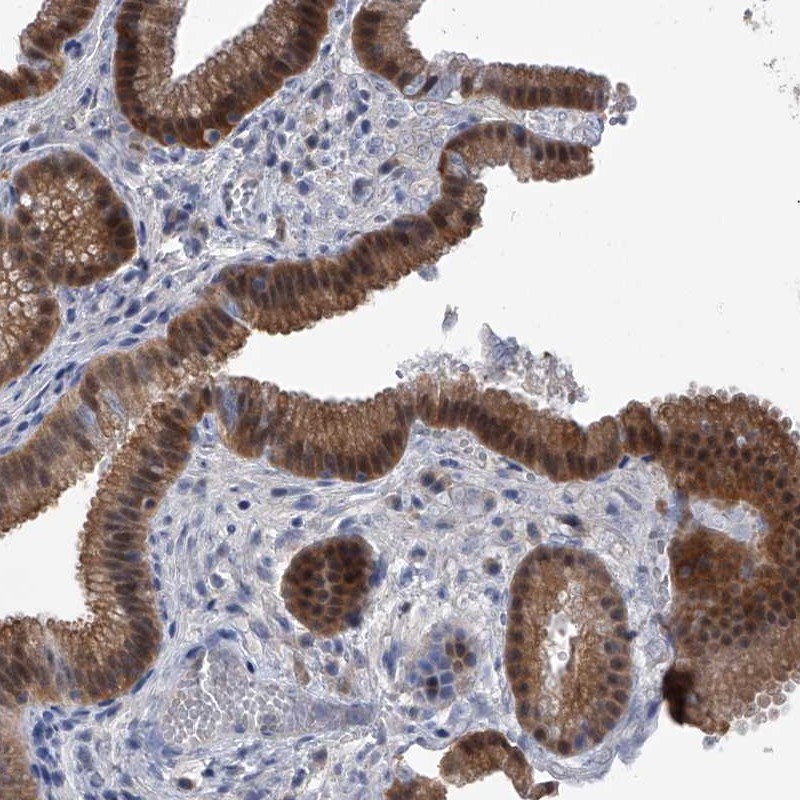

Immunohistochemical staining of human gall bladder shows moderate cytoplasmic and nuclear positivity in glandular cells.